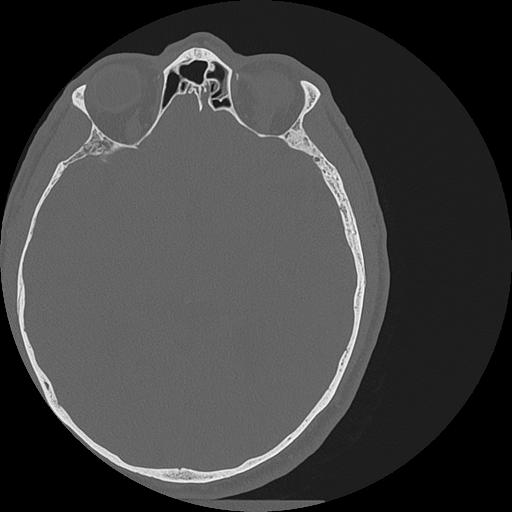

7 HUESO,,Vol,0.5,HUESO,,